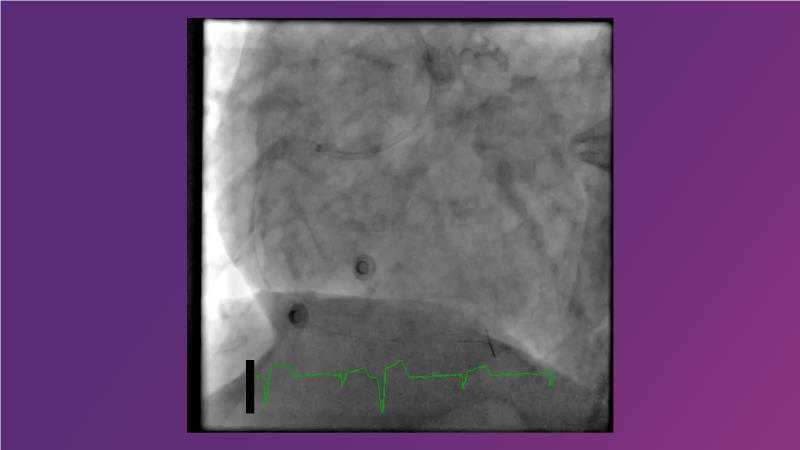

Tune into this 2024 session for insights into the latest ESC guidelines, strategies to prevent and treat no reflow, and an examination of trials like TASTE, TAPAS, and TOTAL on coronary thrombus management. Explore also the outcomes of the CHEETAH study, pondering a potential paradigm shift, and delve into a case study on thrombus removal in a patient with high thrombus burden.